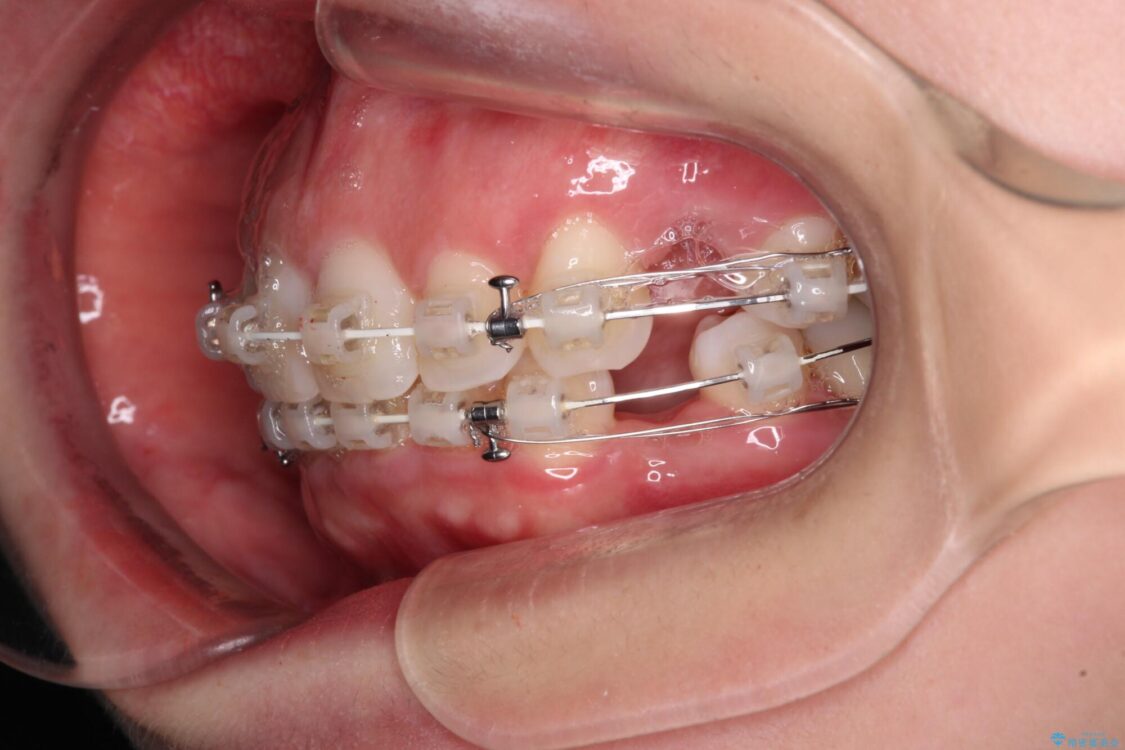

審美装置

左下の大臼歯2本が顕著に舌側に傾斜しているため、まずは奥歯の咬み合わせを改善をし、その後上下左右の第1小臼歯4本を抜歯することで口元を引っ込めながら整えることとしました。

奥歯の咬み合わせ改善には1年ほどの期間と処置中の噛みにくさを強いることとなりましたが、抜歯後はスムーズに治療を完了させることができました。

歯ぎしりの際に奥歯が干渉していた咬み合わせも理想的な状態に改善できました。

治療途中

• 【モニター】出っ歯と咬み合わせを改善 ワイヤー装置の抜歯矯正 治療途中画像